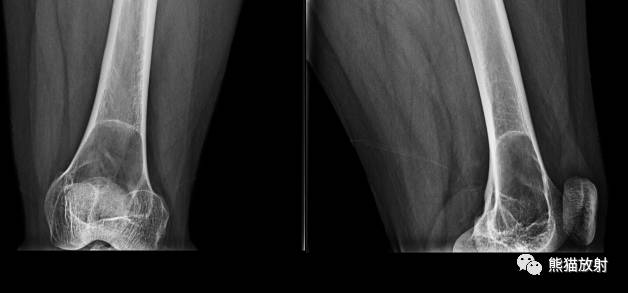

↓ 腓骨近端浆细胞瘤(III型穿透样表现)

III:穿透样